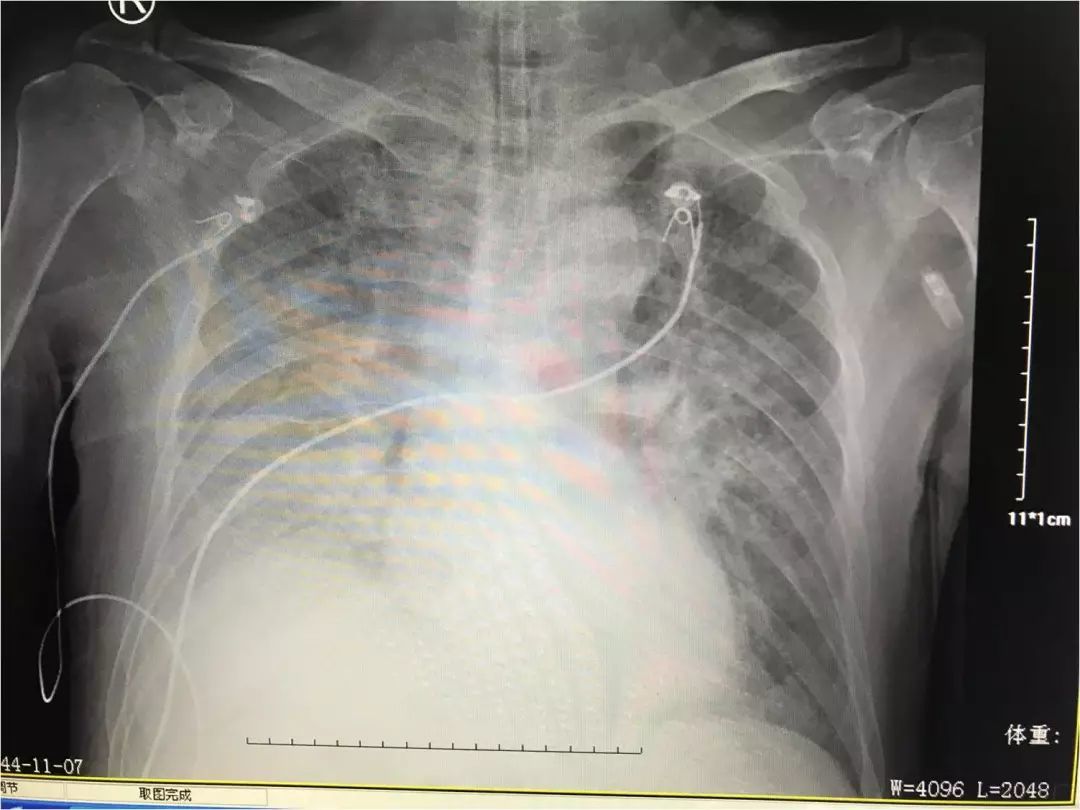

柳叶刀丨一例复张性肺水肿 显示